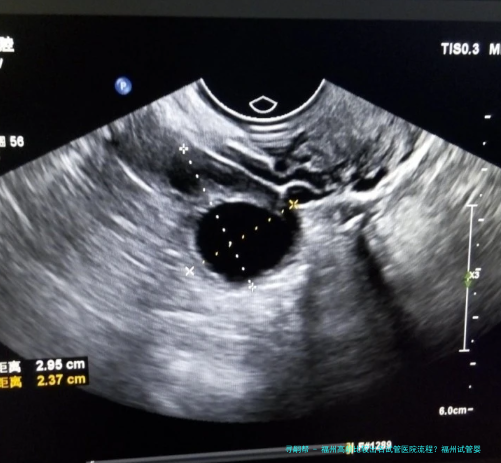

在福州三代试管婴儿医院进行高龄试管婴儿治疗前,病人须要接收诸多的体检和评估。这些检查可以帮助医生了解病人的身体状况和生育情况,为后续治疗提供准确的基础数据。常见的检查项目包括血液常规、甲状腺功能、子宫内膜厚薄程度、输卵管通顺性等。同一时刻仍旧要进行男方精液分析以确定其精子质量和数量。

福州三代试管医院针对每位患者的具体情况制定个性化的高龄试管婴儿医治策略。根据病人年纪、身体条件和生育历史等要点,医生会确定适当的促排方案,并监测激素水平和卵泡成长情形。在促排卵过程当中医生将使用无痛微小创伤技术,保障手术的安全和成功。另外福州三代试管婴儿医院还选用尖端的胚胎培养技术,提高胚胎着床率和妊娠率。